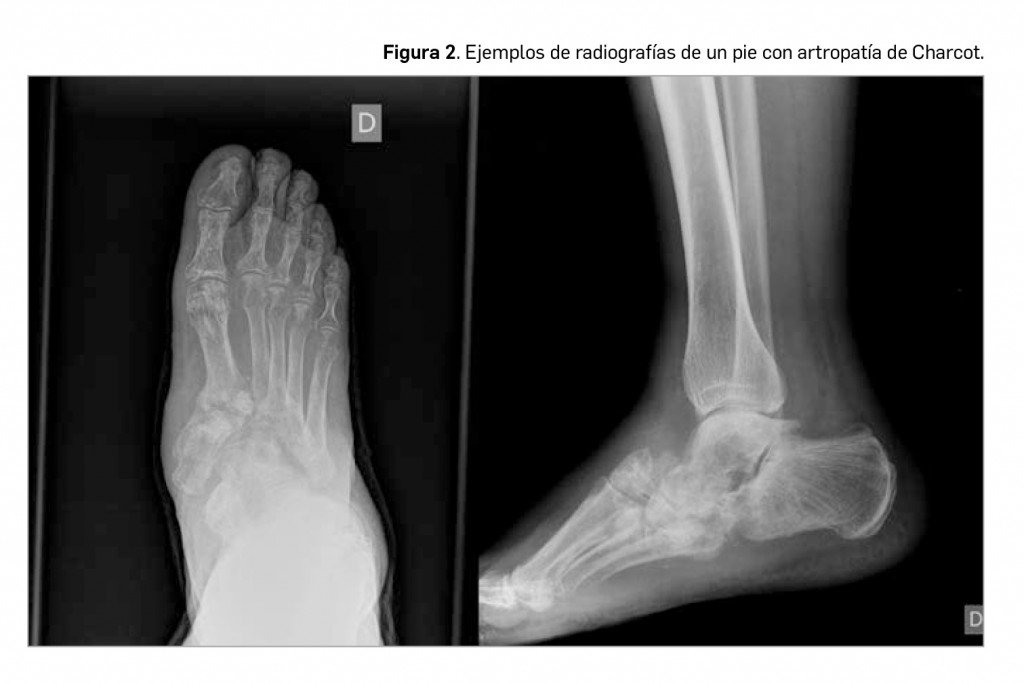

La artropatía de Charcot supone un cuadro clínico, relativamente frecuente y posiblemente infradiagnosticado en multitud de ocasiones. Se traduce en la presentación de una pérdida de sensibilidad en el pie, donde los micro-traumatismos repetidos acaban produciendo una inestabilidad articular, con la aparición de micro fracturas y esclerosis subcondral en los fragmentos óseos afectados como hallazgos típicos de esta patología. Se trata, por tanto, de una forma crónica de artropatía degenerativa asociada a una pérdida de sensibilidad dolorosa térmica y propioceptiva. Aparece con mayor frecuencia en diabéticos, enfermos con siringomielia o en presencia de una tabes dorsal luética. El gran problema es que, debido a su inicio insidioso, con escaso dolor y discretos signos inflamatorios, en muchas ocasiones se producen diagnósticos erróneos (infección, celulitis, distrofia simpático-refleja, artritis séptica, gota, etc.) que implican un retraso en el inicio del tratamiento adecuado.

La fisiopatología de esta entidad no acaba de estar clara. En el diabético posiblemente coexistan varios factores: ante el mal control de la diabetes aparecería una pérdida sensitiva, una neuropatía motora responsable del desequilibrio muscular y una neuropatía autonómica acompañada de osteopenia; esta situación nos presenta un “pie insensible”, incapaz de responder a agresiones por un fallo en la propiocepción. Se debe sospechar la existencia de una artropatía de Charcot en todo diabético mal controlado que presente edema unilateral del pie acompañado de ausencia de dolor y deformidad e inestabilidad articular.

En la radiografía (Figura 2), se pueden observar cambios atróficos (aumento de partes blandas, resorción ósea e incluso pequeñas líneas de fisuración) o hipertróficos (con destrucción articular, subluxaciones o luxaciones francas de los huesos del tarso, destrucción articular y aparición de grandes osteofitos). De cualquier modo, la exploración radiológica es útil cuando la enfermedad ya se encuentra muy avanzada. En estadios precoces se hace necesario la realización de gammagrafía ósea, TAC o resonancia magnética. Estas pruebas de imagen ayudarán a diferenciar esta entidad de otras de presentación clínica similar, como la osteomielitis.

El tratamiento se basa en la descarga articular. En los primeros estadios se puede iniciar un abordaje farmacológico mediante pamidronato. La cirugía tiene escasa cabida en el inicio y se recurre a ella cuando se hace necesario la artrodesis en articulaciones inestables. En conclusión, la neuroartropatía de Charcot es una enfermedad con gran dificultad diagnóstica, ya que no hay criterios definitivos ni pruebas que confirmen su diagnóstico, por lo que, ante la presencia de inflamación y edema del pie en un paciente diabético con neuropatía sensitivo motora en extremidades inferiores, se debe pensar en la posibilidad de neuroartropatía de Charcot.